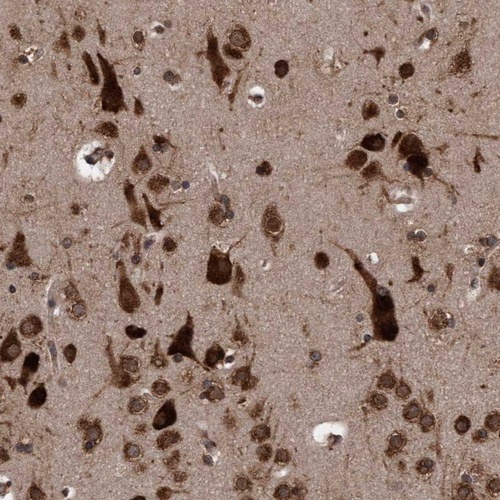

Immunohistochemical staining of human cerebral cortex shows strong cytoplasmic positivity in neurons.